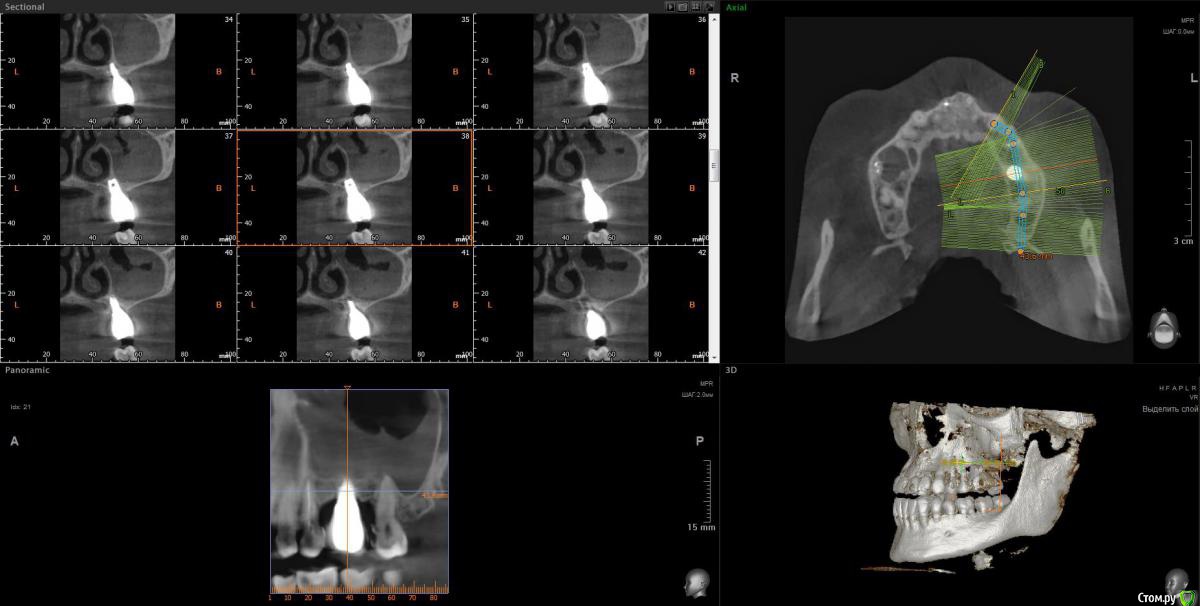

wladdX Опубликовано 9 апреля, 2020 Поделиться Опубликовано 9 апреля, 2020 Несколько скринов Ссылка на комментарий

Lunar Опубликовано 9 апреля, 2020 Автор Поделиться Опубликовано 9 апреля, 2020 Несколько скринов25_1.jpg25_2.jpgimp_1.jpgimp_2.jpg27_1.jpg27_2.jpgспасибо за скрины Ссылка на комментарий

Irouil Опубликовано 9 апреля, 2020 Поделиться Опубликовано 9 апреля, 2020 https://yadi.sk/d/FRKX9i80axqaUgПосмотрел я Ваше КТ. На мой взгляд, проблема чисто ЛОРовская, но... ЛОР врач может придраться к состоянию в полости рта и формально будет прав, поэтому Сначала проверить на витальность 7ку (вероятнее всего все же придётся депульпировать) Клинически осмотреть 5-ку (стоматологу терапевту). Потом к лору. Имплантат к пазухе вообще не имеет никакого отношения 1 Ссылка на комментарий

Irouil Опубликовано 10 апреля, 2020 Поделиться Опубликовано 10 апреля, 2020 Ну, вообще определённые вопросы к имплантату и по КТ, и по фото во рту есть. Но не связанные с пазухой Ссылка на комментарий